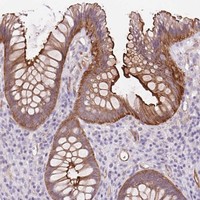

Immunohistochemical staining of human rectum shows strong membranous and cytoplasmic positivity in glandular cells.